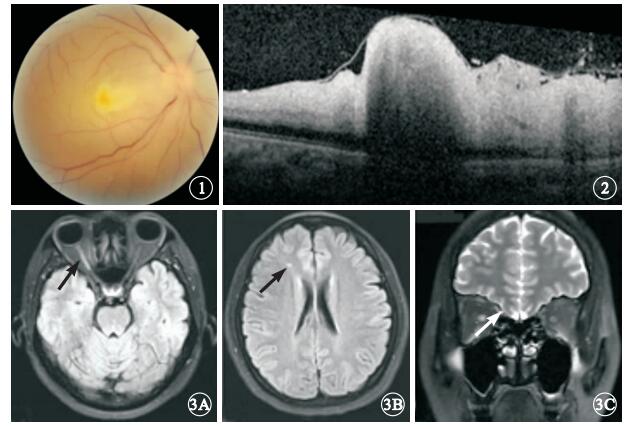

患者女,37歲。行隆鼻手術中突然右眼失明28 h于2013年9月4日來我院就診。患者1 d前在美容院行隆鼻手術,右側鼻根部位注射膠原蛋白0.5 ml,注射醫生在鼻根部注射部位給予按摩后患者隨即出現心悸、頭暈、惡心等不適。醫生判斷為過敏反應給予地塞米松10 mg肌肉注射,患者閉目休息。2 h后患者睜眼發現右眼視物不見,眼球周圍脹痛。當地醫院檢查,右眼視力無光感,眼底視網膜蒼白。診斷視網膜中央動脈阻塞(CRAO),給予硝酸甘油擴張血管等治療。為進一步診治來我院就診。眼科檢查:右眼視力無光感,左眼視力1.2。瞳孔直徑右眼5 mm,左眼3 mm。左眼直接對光反射正常,間接對光反射消失;右眼直、間接對光反射均消失。眼壓右眼8 mmHg(1 mmHg=0.133 kPa), 左眼12 mmHg。右眼上瞼下垂,遮蓋瞳孔上緣1/3,眼球各方向活動均受限;結膜無充血,角膜透明,房水混濁(+)。眼底檢查,視網膜彌漫性水腫,顏色蒼白;黃斑區灰白色隆起,未見櫻桃紅,視盤水腫(圖 1)。左眼眼前節、眼底檢查正常。頻域光相干斷層掃描(SD-OCT)檢查,右眼內層視網膜彌漫性水腫、高度隆起(圖 2)。眼部彩色多普勒檢查,右眼視網膜中央動脈、睫狀后動脈及眼動脈血流均未探及,球后僅探及低速反向眼上靜脈血流信號。眼眶MRI檢查,軸位T2加權見右側視神經全程強信號,后極部視網膜、右眼眶內眼外肌部分強信號;右側額葉點狀缺血灶,彌散加權(DWI)右視神經急性期缺血(圖 3)。因患者對熒光素鈉過敏,未行熒光素眼底血管造影檢查。全身檢查:血壓130/70 mmHg血常規、血糖、血脂和肝腎功能等實驗室檢查未見異常。診斷:右眼醫源性急性眼動脈栓塞。治療:靜脈給予甲潑尼龍琥珀酸鈉240 mg,連續3 d,同時輔以神經保護劑。1個月后隨訪,患者右眼視力無光感;眼前節未見異常;眼底黃斑區水腫消退,視盤下方和鼻側視網膜分支血管閉塞,視盤周圍視網膜前機化膜形成。上瞼高度及眼球運動基本恢復正常。眼壓正常。

圖1

右眼彩色眼底像。視網膜彌漫性水腫,顏色蒼白,黃斑區未見典型櫻桃紅,視盤水腫??圖 2??右眼SD-OCT像。內層視網膜明顯水腫,黃斑部高度隆起??圖 3??頭顱MRI像。3A.軸位T2 Flair加權,右側視神經全程強信號(黑箭);3B.右側額葉點狀缺血灶(黑箭);3C.Stair序列,右側視神經信號異常(白箭)

圖1

右眼彩色眼底像。視網膜彌漫性水腫,顏色蒼白,黃斑區未見典型櫻桃紅,視盤水腫??圖 2??右眼SD-OCT像。內層視網膜明顯水腫,黃斑部高度隆起??圖 3??頭顱MRI像。3A.軸位T2 Flair加權,右側視神經全程強信號(黑箭);3B.右側額葉點狀缺血灶(黑箭);3C.Stair序列,右側視神經信號異常(白箭)

患者女,37歲。行隆鼻手術中突然右眼失明28 h于2013年9月4日來我院就診。患者1 d前在美容院行隆鼻手術,右側鼻根部位注射膠原蛋白0.5 ml,注射醫生在鼻根部注射部位給予按摩后患者隨即出現心悸、頭暈、惡心等不適。醫生判斷為過敏反應給予地塞米松10 mg肌肉注射,患者閉目休息。2 h后患者睜眼發現右眼視物不見,眼球周圍脹痛。當地醫院檢查,右眼視力無光感,眼底視網膜蒼白。診斷視網膜中央動脈阻塞(CRAO),給予硝酸甘油擴張血管等治療。為進一步診治來我院就診。眼科檢查:右眼視力無光感,左眼視力1.2。瞳孔直徑右眼5 mm,左眼3 mm。左眼直接對光反射正常,間接對光反射消失;右眼直、間接對光反射均消失。眼壓右眼8 mmHg(1 mmHg=0.133 kPa), 左眼12 mmHg。右眼上瞼下垂,遮蓋瞳孔上緣1/3,眼球各方向活動均受限;結膜無充血,角膜透明,房水混濁(+)。眼底檢查,視網膜彌漫性水腫,顏色蒼白;黃斑區灰白色隆起,未見櫻桃紅,視盤水腫(圖 1)。左眼眼前節、眼底檢查正常。頻域光相干斷層掃描(SD-OCT)檢查,右眼內層視網膜彌漫性水腫、高度隆起(圖 2)。眼部彩色多普勒檢查,右眼視網膜中央動脈、睫狀后動脈及眼動脈血流均未探及,球后僅探及低速反向眼上靜脈血流信號。眼眶MRI檢查,軸位T2加權見右側視神經全程強信號,后極部視網膜、右眼眶內眼外肌部分強信號;右側額葉點狀缺血灶,彌散加權(DWI)右視神經急性期缺血(圖 3)。因患者對熒光素鈉過敏,未行熒光素眼底血管造影檢查。全身檢查:血壓130/70 mmHg血常規、血糖、血脂和肝腎功能等實驗室檢查未見異常。診斷:右眼醫源性急性眼動脈栓塞。治療:靜脈給予甲潑尼龍琥珀酸鈉240 mg,連續3 d,同時輔以神經保護劑。1個月后隨訪,患者右眼視力無光感;眼前節未見異常;眼底黃斑區水腫消退,視盤下方和鼻側視網膜分支血管閉塞,視盤周圍視網膜前機化膜形成。上瞼高度及眼球運動基本恢復正常。眼壓正常。

圖1

右眼彩色眼底像。視網膜彌漫性水腫,顏色蒼白,黃斑區未見典型櫻桃紅,視盤水腫??圖 2??右眼SD-OCT像。內層視網膜明顯水腫,黃斑部高度隆起??圖 3??頭顱MRI像。3A.軸位T2 Flair加權,右側視神經全程強信號(黑箭);3B.右側額葉點狀缺血灶(黑箭);3C.Stair序列,右側視神經信號異常(白箭)

圖1

右眼彩色眼底像。視網膜彌漫性水腫,顏色蒼白,黃斑區未見典型櫻桃紅,視盤水腫??圖 2??右眼SD-OCT像。內層視網膜明顯水腫,黃斑部高度隆起??圖 3??頭顱MRI像。3A.軸位T2 Flair加權,右側視神經全程強信號(黑箭);3B.右側額葉點狀缺血灶(黑箭);3C.Stair序列,右側視神經信號異常(白箭)